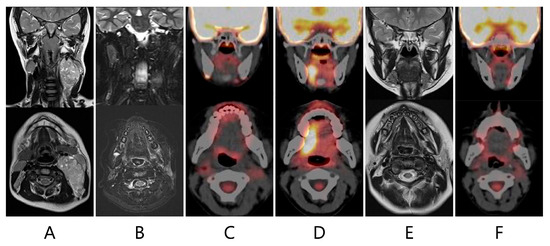

False-Positive Asymmetrical Tongue Muscle 18F-FDG Uptake in Hypoglossal Nerve Paralysis Following Lymph Node Dissection in a Pediatric Patient with Malignant Rhabdoid Tumor of the Neck

by Yuta Matsumoto, Motohiro Matsui, Akari Makidono, Atsushi Makimoto and Yuki Yuza

Children 2024, 11(3), 348; https://doi.org/10.3390/children11030348 - 15 Mar 2024

Cited by 1 | Viewed by 2041

Background: Although positron emission tomography combined with computed tomography (PET-CT) plays an important role in detecting various types of childhood malignancy, it has low positive predictive value, owing to the nonspecific uptake of 18F-fluorodeoxyglucose (FDG) by normal tissue in various benign conditions. Case [...] Read more.

Background: Although positron emission tomography combined with computed tomography (PET-CT) plays an important role in detecting various types of childhood malignancy, it has low positive predictive value, owing to the nonspecific uptake of 18F-fluorodeoxyglucose (FDG) by normal tissue in various benign conditions. Case summary: A 5-year-old male patient with a malignant rhabdoid tumor originating in the left neck underwent primary tumor resection concurrently with ipsilateral lymph node dissection after receiving neoadjuvant chemotherapy consisting of cyclophosphamide, carboplatin, etoposide, vincristine, and doxorubicin. He later received the same adjuvant chemotherapy as well as proton therapy for the primary tumor. Sixteen months after completing the initial therapy, follow-up PET-CT revealed a novel area of glucose hypermetabolism in the right side of the tongue, which was suspected of being a recurrence. However, a physical examination and magnetic resonance imaging (MRI) demonstrated no evidence of tumor recurrence. The patient had a significant leftward deviation of the tongue, suggesting left hypoglossal nerve paralysis. Denervation of the ipsilateral intrinsic tongue muscles secondary to the treatment had caused atrophy in the ipsilateral muscles and compensatory hypertrophy in the contralateral muscles, which increased FDG uptake. Physicians should carefully confirm any diagnosis of a locally recurrent tumor because PET-CT often produces ambiguous findings. Full article